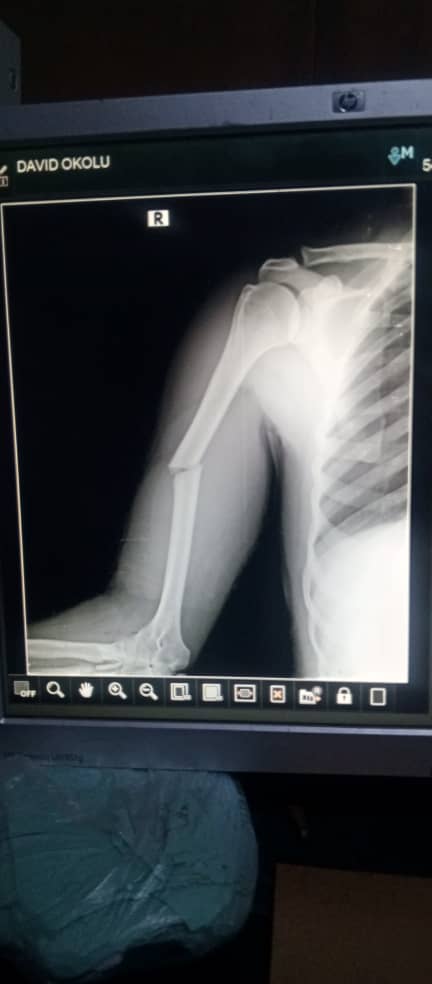

"About ten of the teachers were injured, but four were in critical state as the driver broke his tigh. It took efforts of community people and passersby to revive one of them who was unconscious".